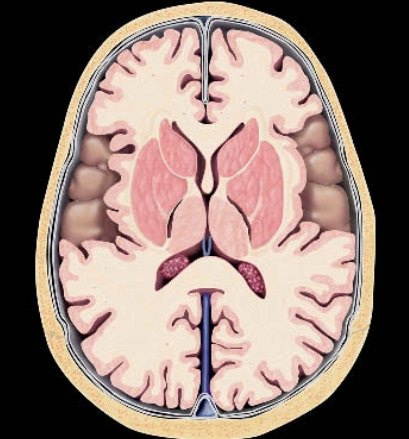

Bệnh não ty thể (Mitochondrial Encephalopathies -ME)

Rối loạn ty thể nguyên phát (Primary mitochondrial disorders - PMDs)

Các biểu hiện ở não của bệnh mucopolysaccharidoses (Cerebral manifestations of mucopolysaccharidoses)

Bệnh loạn dưỡng chất trắng tế bào hình cầu (Globoid Cell Leukodystrophy)/ Bệnh Krabbe

Bệnh Fabry (Fabry Disease)

Rối loạn Peroxisome (Peroxisomal Disorders)/Hội chứng Zellweger (Zellweger Syndrome)

Bệnh nước tiểu mùi si-rô phong (Maple syrup urine disease - MSUD)

Bệnh Canavan (Canavan Disease)

Bệnh loạn dưỡng chất trắng thượng thận liên kết nhiễm sắc thể X (X-linked Adrenoleukodystrophy)

Nhiễm toan glutaric type 1 (Glutaric aciduria type 1)

Bệnh Loạn dưỡng chất trắng thể não to kèm nang dưới vỏ (Megalencephalic Leukoencephalopathy with Subcortical Cysts - MLC)

Thoái hóa thần kinh với tích tụ sắt trong não (Neurodegeneration with Brain Iron Accumulation - NBIA)

Thoái hóa thần kinh liên quan đến Pantothenate Kinase (Pantothenate kinase-associated neurodegeneration - PKAN)

Huntington Disease - HD

Bệnh loạn dưỡng chất trắng dị sắc (Metachromatic Leukodystrophy - MLD)

Bệnh Wilson- Biểu hiện ở não bộ (Wilson Disease)